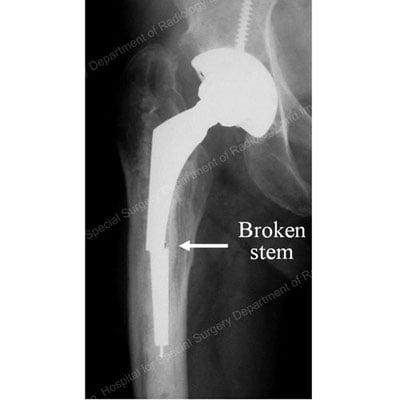

X-ray image showing broken stem section of a total hip replacement prosthesis.

X-ray detailing the broken stem section of a total hip replacement prosthesis